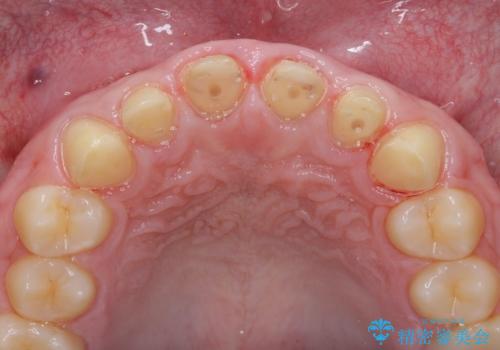

- 「前歯の見た目、歯ぐきの腫れを改善したい。」と希望され来院されました。

前歯には接着性の維持装置や、中途半端な形の連結クラウンが装着され、清掃性が悪く歯ぐきの腫れや、歯ぐきの形態の不揃いが認められました。

ただ、白いオールセラミッククラウンを製作・装着するのではなく、将来にわたり安定した状況を獲得するため、歯周外科を行い歯ぐきと周囲の歯槽骨の形態を整えていきます。

歯周外科を行ったことで、歯ぐきの形態や腫れが改善され、審美性だけでなく清掃性も大きく改善することができました。